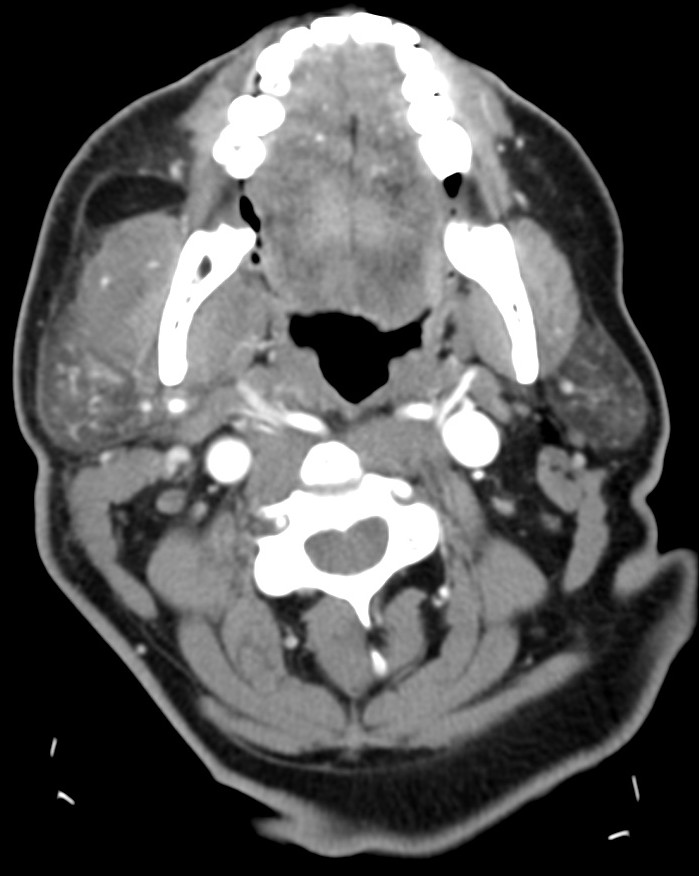

Amigdalitis, Absceso periamigdalino y parafaríngeo:

La clínica no permite diferenciar con exactitud entre celulitis y absceso y no permite determinar con exactitud la extensión del proceso. Clínicamente se sospecha un absceso cuando existe dolor en región cervical y amígdalas que empeora progresivamente a pesar de antibióticoterapia oral, fiebre persistente, odinofagia, voz gangosa, adenopatías cervicales dolorosas y en algunas ocasiones trismus.

Hallazgos:

- Aumento de tamaño de las amigdalas (amigdalas «besándose») con aumento de realce tras tras aplicación de contraste iv.

- En fases avanzadas surgen hipodensidades parenquimatosas o colecciones líquidas debido al edema y la celulitis existente.

- Un absceso periamigalino se diferencia de la celulitis porque presenta una licuefacción/colección central con anillo periférico realzado que puede o no presentar burbujas de aire en su interior. Un absceso de morfología irregular indica estadio más evolucionado.

- El absceso puede extenderse al espacio parafaringeo, constituye el 9% de todas las masas parafaríngeas.

- La distinción entre celulitis y absceso es importante en lo que al tratamiento se refiere. Si existe una colección drenable, la aspiración es el tratamiento requerido. Una colección con anillo periférico realzado, es compatible con absceso drenable en el 63-77% de los casos, población pediátrica y adulta incluida.

- Puede observarse agrandamiento y realce de la úvula.

- Es frecuente identificar adenopatías cervicales.

- Es frecuente observar una mala delimitación de los tejidos blandos adyacentes y las adenopatías cervicales.

- Una vez que la infección ha remitido, pueden quedar calcificaciones residuales en la amígdala.